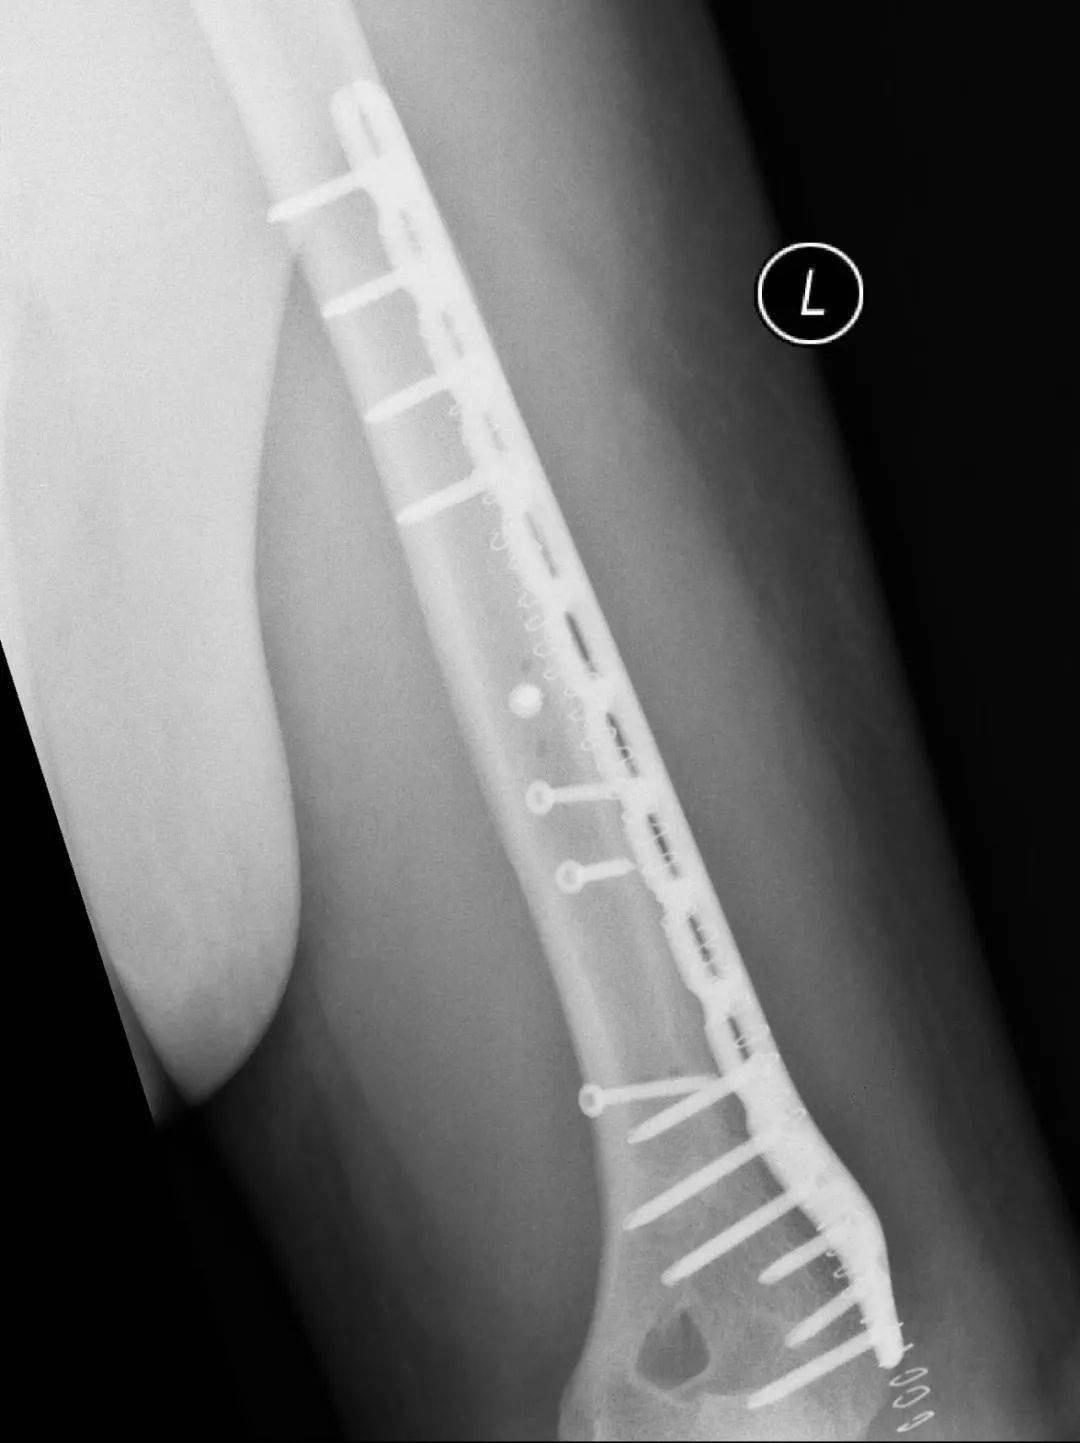

肱骨干骨折的治疗方法包括非手术治疗、闭合复位髓内钉内固定术和切开复位钢板螺钉内固定术等多种方式。采用非手术治疗时,可对患肢进行悬垂石膏固定或行闭合复位后使用上臂U型石膏固定,2-3周后解放肘关节,使用功能支具固定10-12周。由于扳手腕导致的肱骨干骨折几乎均为肱骨远端三分之一螺旋形骨折,闭合复位髓内钉内固定术不适合这类骨折,切开复位钢板螺钉内固定术是这类骨折的最佳的手术治疗方式。

图 切开复位钢板螺钉内固定术